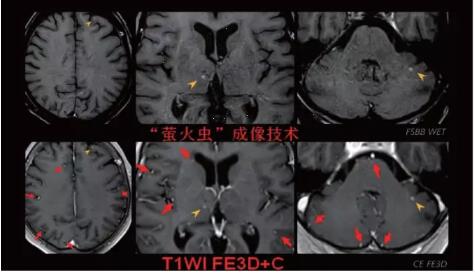

見所未見 微小腫瘤無處遁藏——

“螢火蟲”成像技術(shù) 顱內(nèi)腫瘤微小病灶檢出新發(fā)現(xiàn)

此技術(shù)主要用于神經(jīng)系統(tǒng)惡性腫瘤,以及其他腫瘤腦轉(zhuǎn)移瘤篩查。傳統(tǒng)情況下做腫瘤腦轉(zhuǎn)移篩查,很容易漏掉5mm以下小病灶,臨床發(fā)現(xiàn)后干預(yù)治療比較晚,要實(shí)現(xiàn)2mm高空間分辨率和超薄層全腦掃描在保證信噪比的情況下需要很長時間大概十多分鐘,而且薄層增強(qiáng)序列顱內(nèi)血管呈高亮信號,會干擾顱內(nèi)小病灶的觀察,血管和小病灶區(qū)分困難。佳能”螢火蟲”成像技術(shù)既可以實(shí)現(xiàn)高空間分辨率和超薄層(最薄可實(shí)現(xiàn)0.2mm)全腦掃描,掃描時間短,2-3分鐘即可實(shí)現(xiàn)全腦3D掃描,同時避免了血管高亮信號的干擾,對顱內(nèi)原發(fā)或繼發(fā)的微小腫瘤檢查有重大意義。“螢火蟲”成像技術(shù)具有磁敏感效應(yīng),對于亞急性血敏感敏感,可以區(qū)分出血和強(qiáng)化的腫瘤。